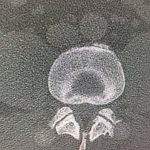

Εικόνα 4 α,β,γ,δ, Αξονική τομογραφία της Ο.Μ.Σ.Σ. (Σεπτέμβριος 2017) μετωπιαίες λήψεις (coronal) ε,στ,ζ,η, οβελιαίες λήψεις (saggital) θ,ι, εγκάρσιες λήψεις (axial). Παρατηρείται η σημαντική οστική αραίωση εντός του σώματος του 1ου οσφυϊκού σπονδύλου.